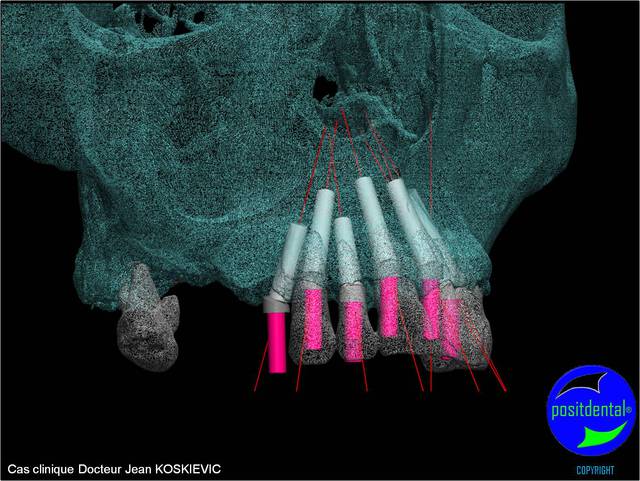

et la projet 10 implants maxillaire sup

10 en haut

donc ce sera minimum 8 en fonction du scan